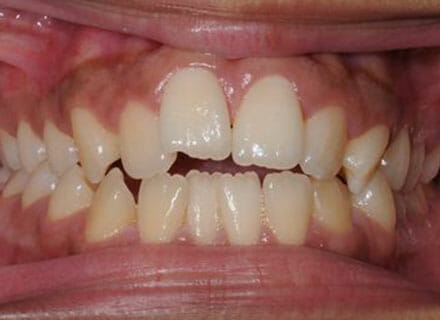

This patient came to us because she hated her smile: it was too narrow, the upper front teeth were all crowded into each other and twisted. She couldn’t eat a sandwich properly with the front teeth because of the gap – the open bite. We were able to expand both jaws to make space to align all the teeth without having to extract – in about 18 months using clear brackets.